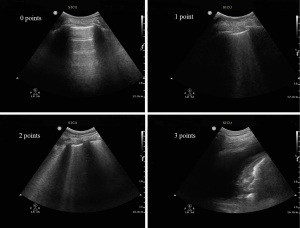

Ultrasound examination

LUS was performed using a convex array 2–5 MHz transducer (Philips CX50) by two trained physicians following a standardized protocol. The thoracic area was divided into 12 quadrants based on the anterior and posterior axillary lines, with further subdivision using the nipple line as a reference for upper and lower segments (13). Each quadrant was independently scored on a scale of 0 to 3, where 0 indicated normal aeration and 3 indicated complete loss of lung aeration (Figure 1). The LUSS was calculated by summing the scores of all quadrants, with higher scores indicating greater lung aeration impairment. Discrepancies in scoring were resolved through discussion, with final interpretation provided by a senior physician with over ten years of clinical ultrasound experience.